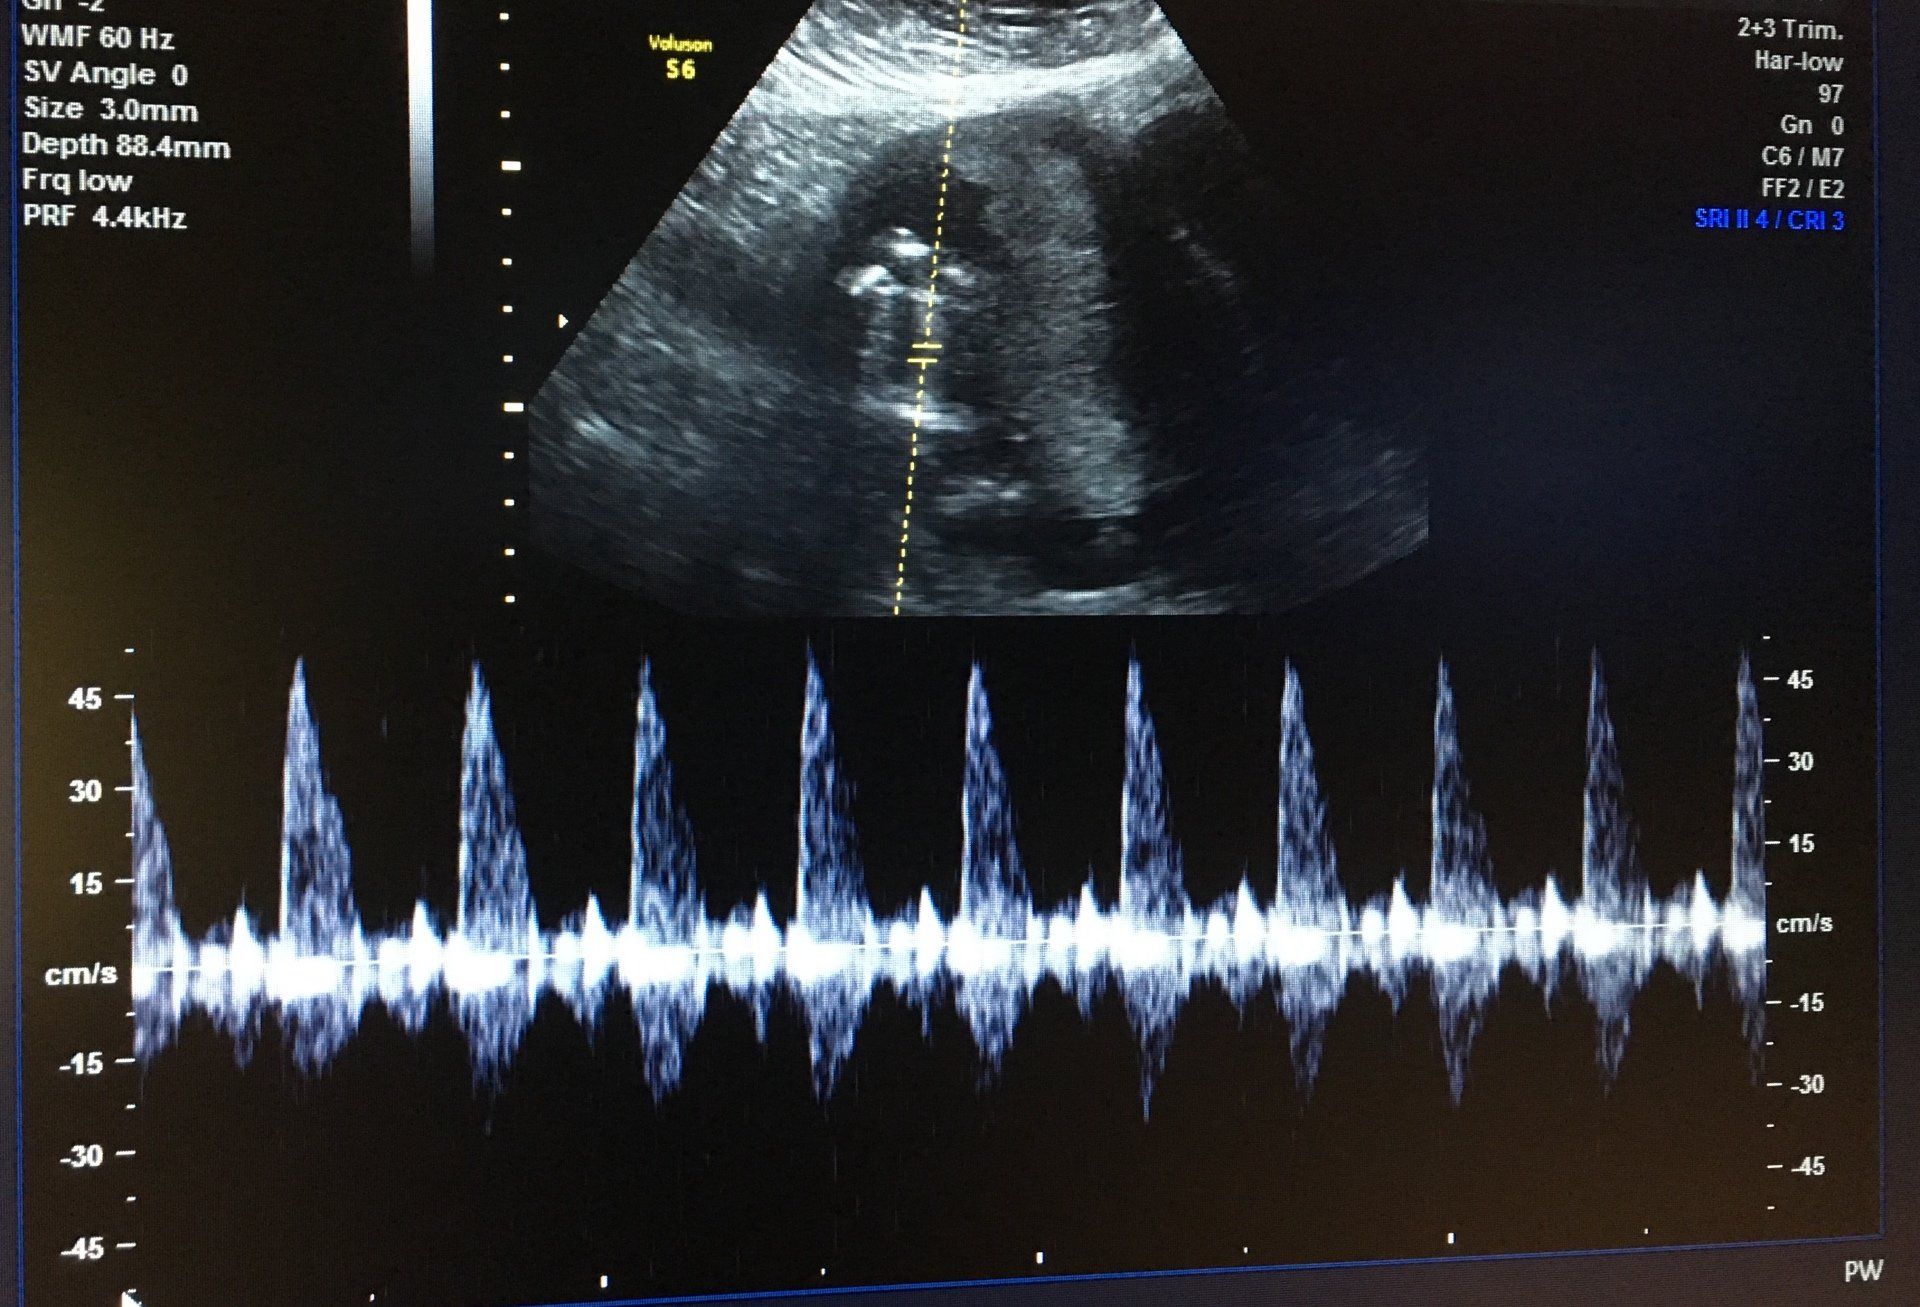

Ultrasound

We strive to provide all families with peace-of-mind and comfort in seeing their baby grow via ultrasound. From the confirmation of a beating heart, finding out if it is a HE or SHE, to the later stage chubby cheeks, we will provide beautiful ultrasound images. We also partner with Sneak Peek to provide early gender determination via DNA as early as 6 weeks gestation!